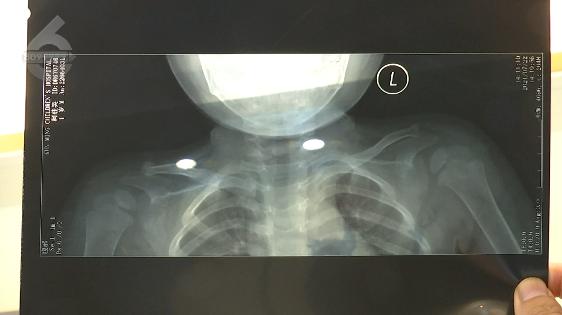

小區(qū)里散步 1歲8個(gè)月孩子跌入7米深通風(fēng)口!全身多處骨折!肺部挫傷

陳女士:“頭部有骨折,還有手臂有骨折,肺部有挫傷。就是小孩一歲八個(gè)月,還在長(zhǎng)身體的時(shí)候!

由于通風(fēng)井深度有7米左右,孩子受傷嚴(yán)重,經(jīng)過救治,費(fèi)用達(dá)到了8000多元,而后續(xù)孩子的治療和康復(fù),還遠(yuǎn)不止這個(gè)數(shù)。